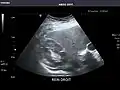

Renal ultrasonography

Ultrasonography of the kidneys is essential in the diagnosis and management of kidney-related diseases. The kidneys are easily examined, and most pathological changes in the kidneys are distinguishable with ultrasound.[7]

Kidneys: Right and left kidneys measure 11.5 cm and 12 cm in length respectively. No hydronephrosis. Small left lower pole kidney cyst.

Right kidney -